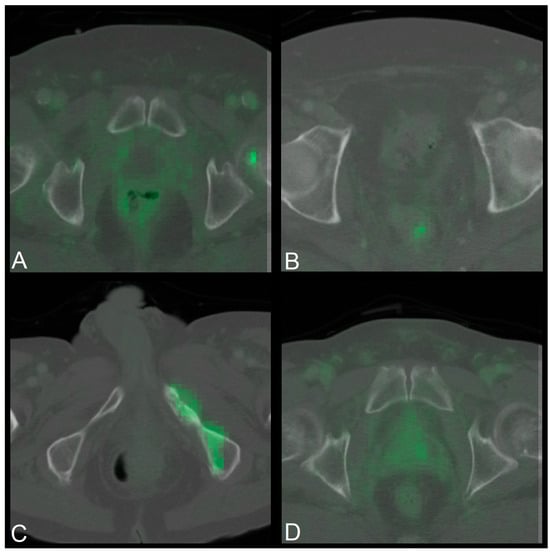

Appendix A.2.5. Manual Inspection of PET/CT Scans

Approximately 100 PET/CT images were inspected manually using the software Napari [33] to determine which features the model struggles with and what else could be done to improve the accuracy of the model. It was noted that region of interest (ROI) could be further restricted around the prostate (area) and that PET signals are also very common in the UB, hip bones and colon. The PET signals occurring in the colon in particular were often similar in size to those visible in the prostate in the case of confirmed local recurrence. Another challenge for the model could be that the prostate and UB are in close proximity which leads to the PET signal of the prostate and UB flowing into each other. A few examples can be seen in the following Figure A2.

Figure A2. NIfTI examples that might show reasons why the model makes mistakes.

Cancers 17 01575 g0a2

Four NIfTIs that show different potential reasons for errors made by the model. PET signal present in contents of the colon at different positions and sizes (A)(B), hip bones showing PET signal (C), and a smooth transition of the PET signal of the prostate (area) and the PET signal of the UB (D). As in Figure A1, the ventral side of the patients is at the top of the images, while the dorsal side of the patients is at the bottom. The CT layer of the images is in greyscale, while the PET layer is shown in green.

Based on these observations, the decision was made to try modifying the ROI and masking certain areas in order to potentially improve the accuracy of the model.